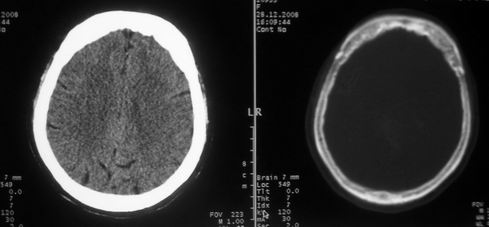

女,72岁,头晕。额骨有无问题。

考虑额骨良性骨板肥厚;骨纤待排。

左额部骨瘤

额骨呈磨玻璃状增厚,考虑骨纤。

额骨呈磨玻璃状增厚,考虑骨纤